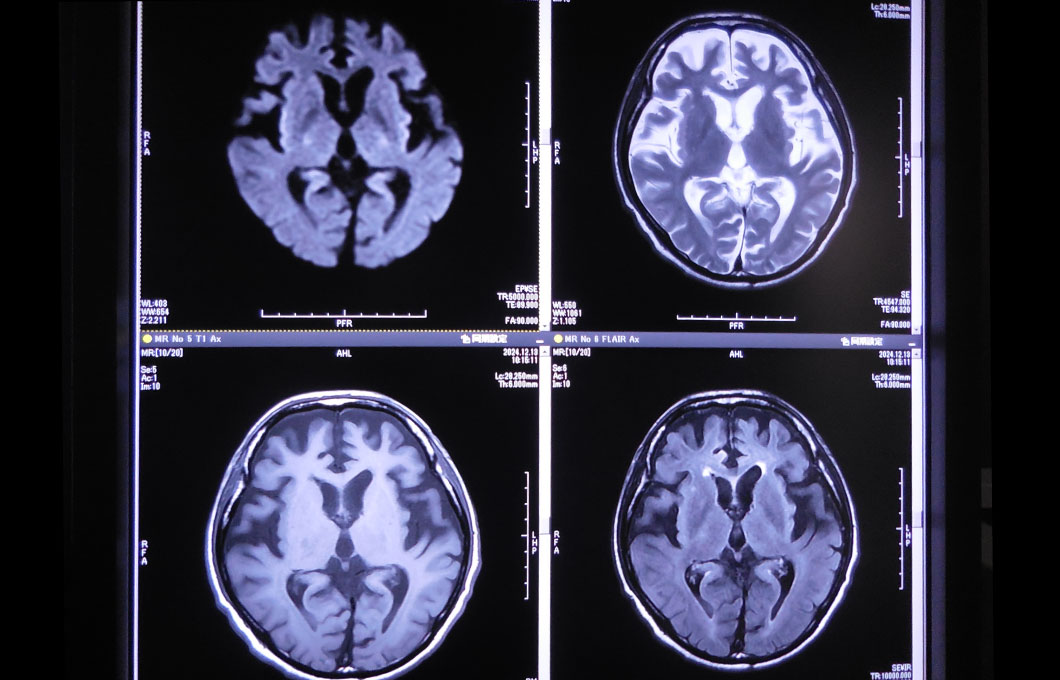

磁気共鳴画像といい、患者さまにトンネル内にある大きな磁石の中に入っていただき、磁気を利用してさまざまな断層像を写し出すことにより、より細やかな診断ができます。この検査の特徴は、X線を使用しないため放射線による被ばくがないことです。